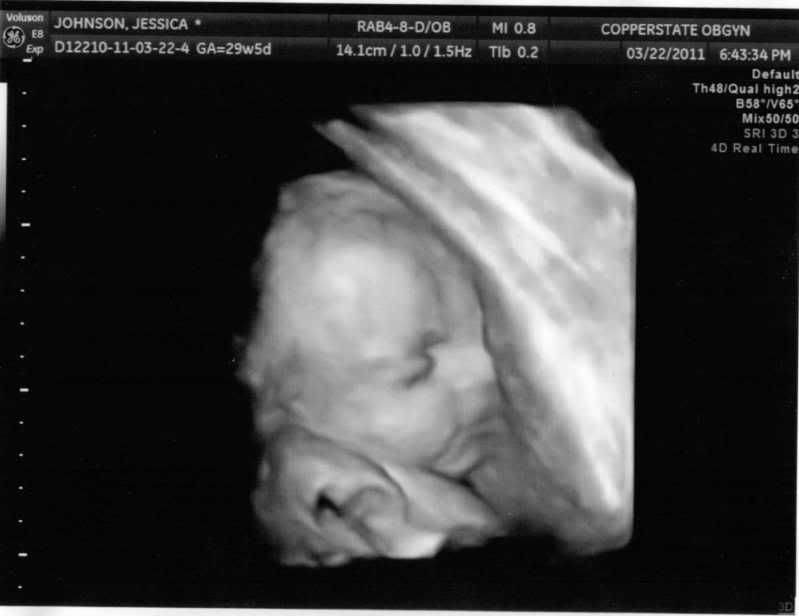

My Husband and I started trying to build our family (secretly of course) around summer of last year. It took us until September to get pregnant and I got my first of MANY positive pregnancy tests on September 18, 2010. I was thrilled, scared, excited and pretty much every emotion you could have. I was given a due date of June 2, 2011 by my OB on October 6, 2010 (there's more to this date..but i'll save you the over-detailed explanation). The first two months of my pregnancy was scary, we weren't sure if the baby was going to "stick" or not and so we kept it quite but told family on a trip to California in Mid October. Here is our little guy's first picture.

The months I've been pregnant have seemed to fly by looking back. I was always waiting for the other shoe to drop thinking that I hadn't done what I needed to do in my life to justify such a blessing. Apparently, I did something right, because the baby has grown from that little bean that you see in this picture to a full term baby.